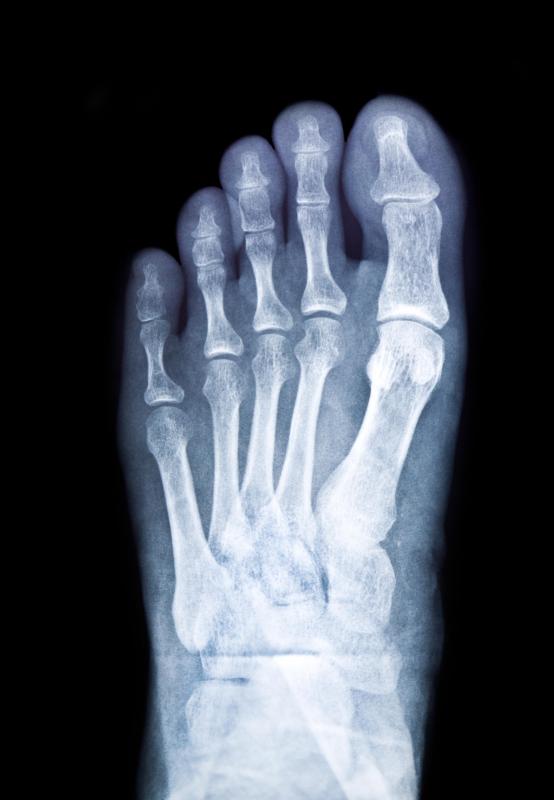

Fractured Foot, Xray Photograph by Du Cane Medical Imaging Ltd Pixels Stress Fracture Toes Symptoms While this type of fracture commonly. The key symptom of a stress fracture is pain. Repetitive stress on your toe can cause a tiny hairline break called a stress fracture. Pain that starts and gets worse during physical activity. The most common symptoms of a stress fracture include: What are the symptoms of a stress fracture in the foot and. Stress Fracture Toes Symptoms.